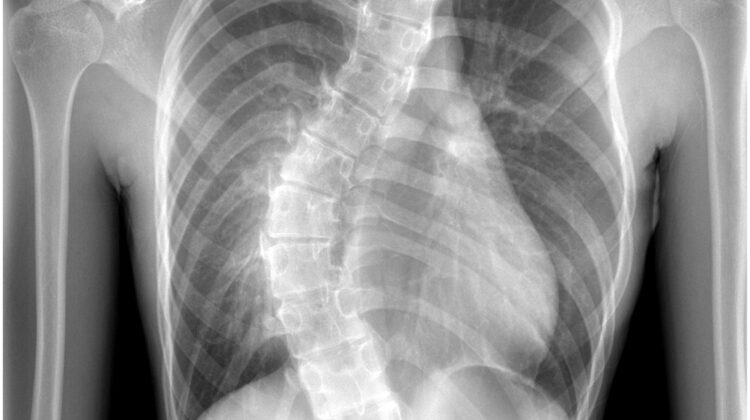

يعاني بعض الأطفال والمراهقين من اعوجاج في العمود الفقري، وهو انحناء جانبي قد يظهر خلال فترة النمو السريع. بعد زيارة الطبيب وإجراء الأشعة، غالبًا ما يجد الأهل صعوبة في فهم ما تعنيه الأرقام والمصطلحات الطبية في التقرير. في هذا المقال سنشرح بطريقة بسيطة كيفية قراءة تقرير الأشعة وما يجب التركيز عليه لفهم حالة الطفل بشكل أفضل.

الأشعة الأكثر استخدامًا لتشخيص اعوجاج العمود الفقري هي الأشعة السينية (X-ray)، وأحيانًا يُستخدم تصوير بالرنين المغناطيسي (MRI) إذا احتاج الطبيب لفحص الأعصاب أو الأقراص بين الفقرات.

زاوية كوب (Cobb Angle):

يقيس درجة انحناء العمود الفقري بالدرجات.

كلما زادت الزاوية، زاد الانحناء، وقد يحتاج الطفل إلى متابعة أو علاج.

نوع الانحناء (Curve Type):

يشير إلى مكان الانحناء: صدري، قطني، أو مزدوج.

التحيز الجانبي للفقرات (Vertebral Rotation):

يوضح مدى دوران الفقرات حول نفسها نتيجة الانحناء.

يؤثر على شكل القفص الصدري والكتفين.

خطوط التوازن (Plumb Line):

تقيس ما إذا كان العمود الفقري متوازنًا عند الوقوف.

أي انحراف عن الخط الطبيعي قد يشير إلى ضرورة متابعة دقيقة أو تدخل علاجي.